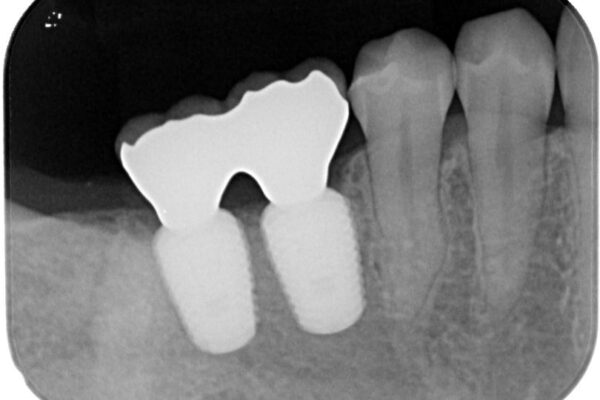

インプラント希望部位は右下第一大臼歯と第二大臼歯です。

しかし、噛み合わせの相手である右上の第二大臼歯が、長期間噛み合う歯がなかった影響で**挺出(歯が下に伸びてくる状態)してしまっており、このままではインプラントを埋入して被せもの(上部構造)を入れるためのスペースが不足している状態でした。

そこで、右上の奥歯に部分的なワイヤーを装着し、さらに矯正用アンカースクリュー(TADs)を併用することで、挺出した歯を圧下(歯を元の高さに戻す動き)させ、下顎にインプラントを埋入するための十分な垂直的スペースを確保しました。

スペースが整った段階で、右下の第一大臼歯と第二大臼歯にインプラントを埋入。